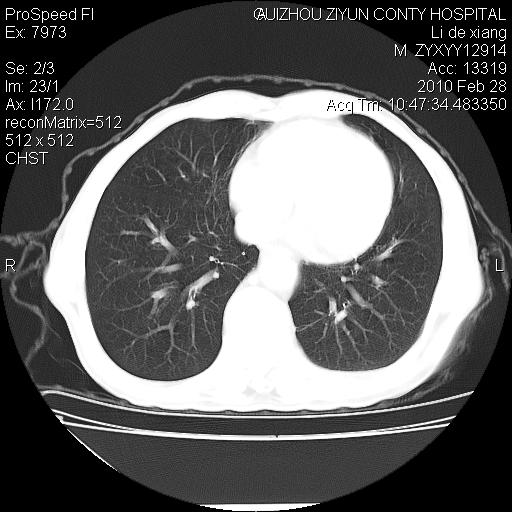

标题: CT24776:男 71Y 咳嗽咳痰胸痛两月,伴声音嘶哑。 [打印本页]

左侧中央型肺癌伴左肺上叶阻塞性肺炎及节段性不张可能性大,建议纤支镜检查!

左侧中央型肺癌伴左肺上叶阻塞性肺炎及节段性不张可能性大,建议纤支镜检查!纵隔淋巴结转移.

左侧中央型肺癌伴左肺上叶阻塞性肺炎及纵隔淋巴结转移。

左肺门部肿块,伴左上肺斑块影,周边模糊,支持左肺中央型肺癌伴节段性不张及阻塞性肺炎,结合支气管镜检查。

左上叶支气管狭窄,阻塞性病变,肺门肿块,纵隔及肺门淋巴结增大,中央性肺癌